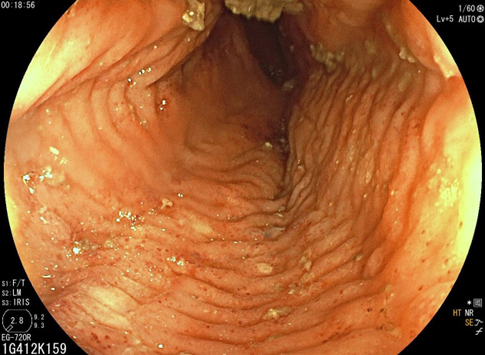

Depuis un an, elle rapporte des crampes d’estomac, notamment après des repas copieux, évoluant par périodes, ainsi qu’un pyrosis nocturne plusieurs fois par semaine. Elle a remarqué dernièrement une gêne thoracique lorsqu’elle boit de l’alcool et lors de ses séances de sport. Il n’y a pas de troubles du transit.

Les crampes épigastriques et la périodicité font partie du syndrome ulcéreux.

Le pyrosis et le syndrome postural sont des signes typiques de RGO.

Cette symptomatologie épigastrique peut être le reflet d’une gastrite